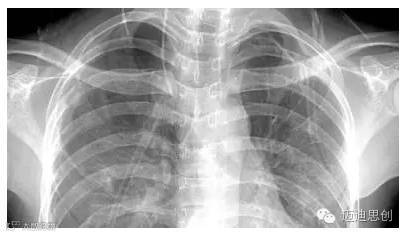

X光:像把面包压扁了看

X光会穿过人体,遇到被遮挡的部位,底片上不会曝光,洗片后这个部位就是白色的。

就像一片面包或一块棉花,看不到里面的纤维纹理,但用手压瘪了会清晰一些。X光最大缺点是受制于深浅组织的影像相互重叠和隐藏,有时需要多次多

角度

拍摄X光片。

3、胸部——粗看X光片,细看CT

X光胸片可粗略检查心脏、主动脉、肺、胸膜、肋骨等,可以检查有无肺纹理增多、肺部钙化点、主动脉结钙化等。

胸部CT检查显示出的结构更清晰,对胸部病变检出敏感性和显示病变的准确性均优于常规X光胸片,特别是对于早期肺癌确诊有决定性意义。但是,CT检查的辐射剂量高于X光。核磁对于肺部疾病的诊断,应用非常有限。